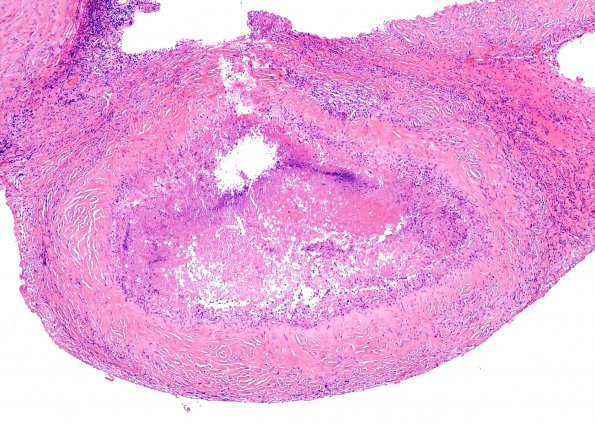

One of the biopsied lesions shows a necrotic center, numerous degenerating PMNs, a thickened collagenous wall and a chronic inflammatory infiltrate with rare giant cells, a histologic image we have designated hyalinizing pyo-granuloma. (H&E)